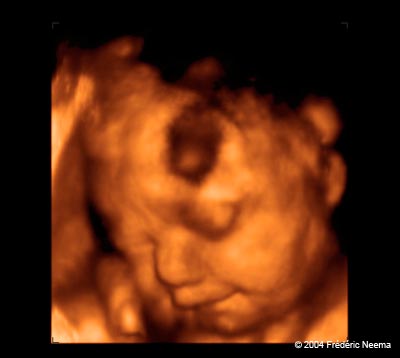

The 3-D image of an unborn child revealed by an ultrasound scan operated at the Prenatal Peek studio in Novato,CA. Expecting mothers can now have a glimpse of what their developing child might look like by going to private studios that offer 3D ultrasound imagery. Relaxing in recliners, with soft music playing in the background, mothers and their families have a chance to meet their babies and walk out with a video or DVD of their experience as well as color photographs. Unlike the classic 2D ultrasound performed by obstetricians to verify the absence of abnormalities, the 3D ultrasounds have no medical value.